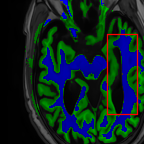

Sparsity LI 2D CNN 3D CNN Ours GT

4 Refer to caption (a) 0.6787/0.7972 Refer to caption (b) 0.8143/0.8776 Refer to caption (c) 0.8190/0.8714 Refer to caption (d) 0.8664/0.9085 Refer to caption (e) GM/WM

Refer to caption (f) 0.6808/0.7161 Refer to caption (g) 0.8103/0.8631 Refer to caption (h) 0.7950/0.8606 Refer to caption (i) 0.8598/0.9115 Refer to caption (j) GM/WM

8 Refer to caption (k) 0.5139/0.7240 Refer to caption (l) 0.6619/0.8224 Refer to caption (m) 0.6878/0.8584 Refer to caption (n) 0.7798/0.8853 Refer to caption (o) GM/WM

Refer to caption (p) 0.5910/0.6947 Refer to caption (q) 0.6516/0.8021 Refer to caption (r) 0.6507/0.8186 Refer to caption (s) 0.7471/0.8540 Refer to caption (t) GM/WM

Figure 6: Visual comparison of gray matter (Green)/white matter (Blue) segmentation over different methods, with respective DICE scores listed under the images.

In Fig. 6, we demonstrate the advantage of the proposed method in brain matter segmentation. It is clear that although 2D and 3D CNN generates visually plausible interpolation as presented in Fig. 5, the brain matters are easily misclassified due to incorrect anatomical structures and blurred details.